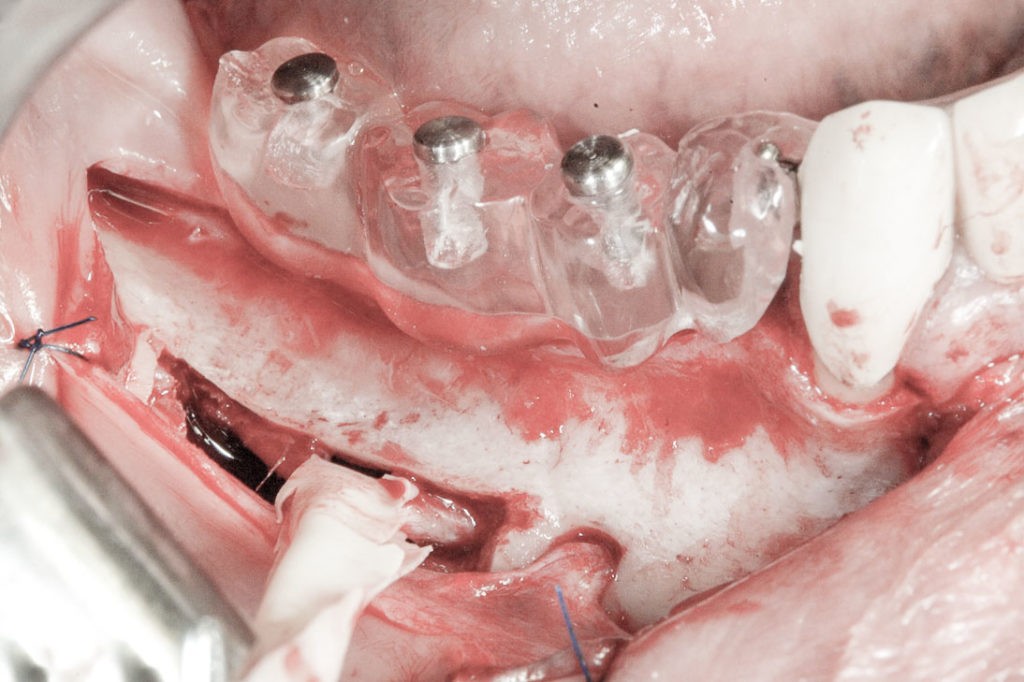

To kolejna metoda umożliwiająca precyzyjną odbudowę zadanego kształtu tkanki kostnej przy użyciu standardowych materiałów kościotwórczych, kości własnej lub PRF oraz zewnętrznego rusztowania w postaci siatki z biozgodnego stopu tytanu. Siatka jest indywidualnie projektowana w technologii CAD CAM i następnie drukowana dla konkretnego przypadku.

Dotychczas stosowane stabilizatory zewnętrzne w formie siatek tytanowych używane do regeneracji kostnej lub w zabiegach odtwórczych w chirurgii szczękowo-twarzowej uwzględniały materiały ręcznie doginane i formowane podczas zabiegu operacyjnego. Zastosowanie technologii CAD CAM dla potrzeb druku materiałów przeznaczonych do indywidualnej rekonstrukcji kostnej znacznie poprawiło precyzję i jakość uzyskiwanych efektów. Wdrożenie biozgodnych stopów tytanu do druku siatek zdecydowanie ograniczyło odsetek powikłań zapalnych.

Siatki stanowią stabilną obudowę – ograniczenie nadające kształt regenerowanej kości przy użyciu upakowanego pod nią materiału. Utrzymują i stabilizują rozdrobniony granulat kościotwórczy, co jest warunkiem prawidłowego procesu gojenia, jednocześnie nadając anatomiczny kształt i zakres odbudowie kostnej sprzed jej zaniku.

Precyzja projektu druku siatki bazuje na dokładności odwzorowania kształtu kości w stożkowej tomografii komputerowej CBCT, co zapewnia ich dobre przyleganie do podłoża kostnego oraz ogranicza powstawanie powikłań w postaci obnażania się siatek.

Precyzja projektu oraz materiał, z którego wykonana jest siatka (biozgodny stop tytanu), powodują, że obnażenie się siatki nie zaburza procesu gojenia i regeneracji kostnej. Wymaga jedynie większej ilości kontroli pozabiegowych oraz wzmaga czujność higieniczną zarówno ze strony lekarza, jak i pacjenta.

Ten rodzaj odbudowy kostnej stosowany jest w sytuacjach złożonych, trójwymiarowych 3D ubytków kości, przy których standardowe metody odbudowy są niewystarczające. Ilość kości, którą możemy uzyskać, stosując tę metodę, to nawet kilka centymetrów sześciennych.

Metoda rekonstrukcji kostnej w oparciu o indywidualnie drukowane siatki z tytanu dla implantacji wszczepów śródkostnych stosowana jest najczęściej jako dwuetapowa. W pierwszym etapie odbudowywana jest kość, natomiast implanty wszczepiane są po okresie 4–6 miesięcy. Na wgojenie implantów oczekujemy od 4 do 6 miesięcy w zależności od miejsca ich lokalizacji. Siatka tytanowa po spełnieniu swojej funkcji rusztowania dla odbudowującej się kości jest następnie usuwana w dniu wszczepienia implantu. Jeżeli kość spełnia odpowiednie warunki, istnieje możliwość zastosowania modyfikacji siatki tytanowej, która umożliwia jednoczesne wprowadzenie implantów wraz z odbudową kostną. Wariant ten skraca czas od pierwszego zabiegu do wykonania gotowych koron protetycznych na wprowadzonych implantach.